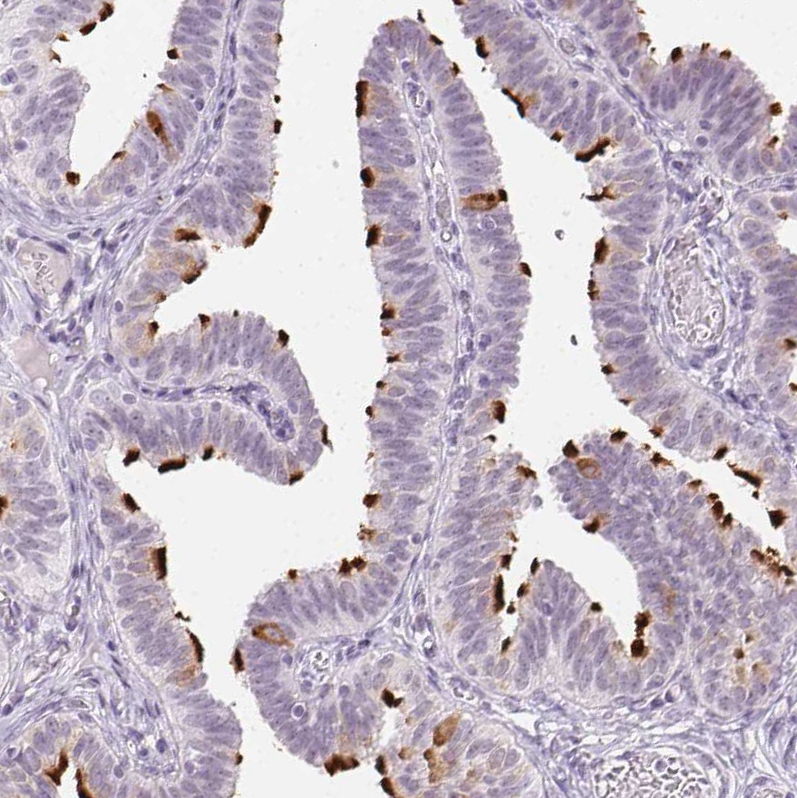

Immunohistochemistry analysis in human testis and prostate tissues using HPA041830 antibody. Corresponding ROPN1L RNA-seq data are presented for the same tissues.